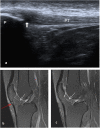

Methods and results: A prospective study was conducted on 143 patients with clinically confirmed AKP. All patients underwent ultrasonography and MRI examinations of the knee. The diagnostic accuracy of ultrasonography compared to MRI for evaluating different findings of possible causes of AKP were analyzed using receiver operating characteristic (ROC) curve and judged by area under curve (AUC). A total of 155 knees were included in the study; 26 knees showed no abnormalities, 19 knees showed positive MRI only, and 110 knees showed positive ultrasonography and MRI. Ultrasonography and MRI reported 11 different findings of possible causes of AKP or related to it. Joint effusion was the most common finding (38%) followed by trochlear cartilage defect (20.6%) and superficial infrapatellar subcutaneous edema (20%). The overall accuracy of ultrasonography was 85.3% sensitivity and 100% specificity. The ultrasonography provided the highest sensitivity (100%) in detecting bipartite patella, followed by 91.5% for joint effusion, and 87.5% for quadriceps tendinopathy. The ROC curve analysis of overall accuracy of ultrasonography showed an AUC of 0.93. The overall Kappa agreement between ultrasonography and MRI was good (k = 0.66).